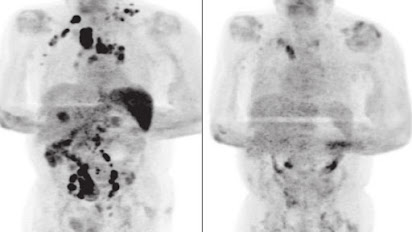

O homem passou 11 dias internado e recebeu alta para se recuperar em casa. Quatro meses depois, a avaliação médica indicou que o linfoma havia reduzido e exames revelaram resolução generalizada da linfadenopatia.

A quantidade do vírus Epstein-Barr reduziu de 4.800 cópias/mL para 413 cópias/mL.